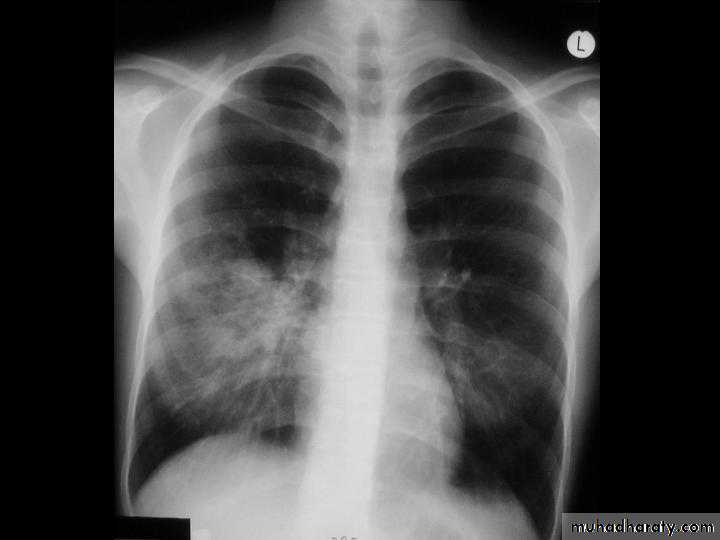

A chest X-ray is usually sufficient to confirm the clinical diagnosis of pneumonia.

In lobar pneumonia, a homogenous opacity localized to the affected lobe or segment usually appears within 12 – 18 hours of the onset of illness.

Chest X-ray helps in:• Differentiating CAP from other diagnosis

• Provide information about severity (cavitation and multilobar involvement)

• Detects complications (pleural effusion or abscess formation).

• It can occasionally suggest an aetiological agent (pneumatocoele in Staphylococcus aureus pneumonia).